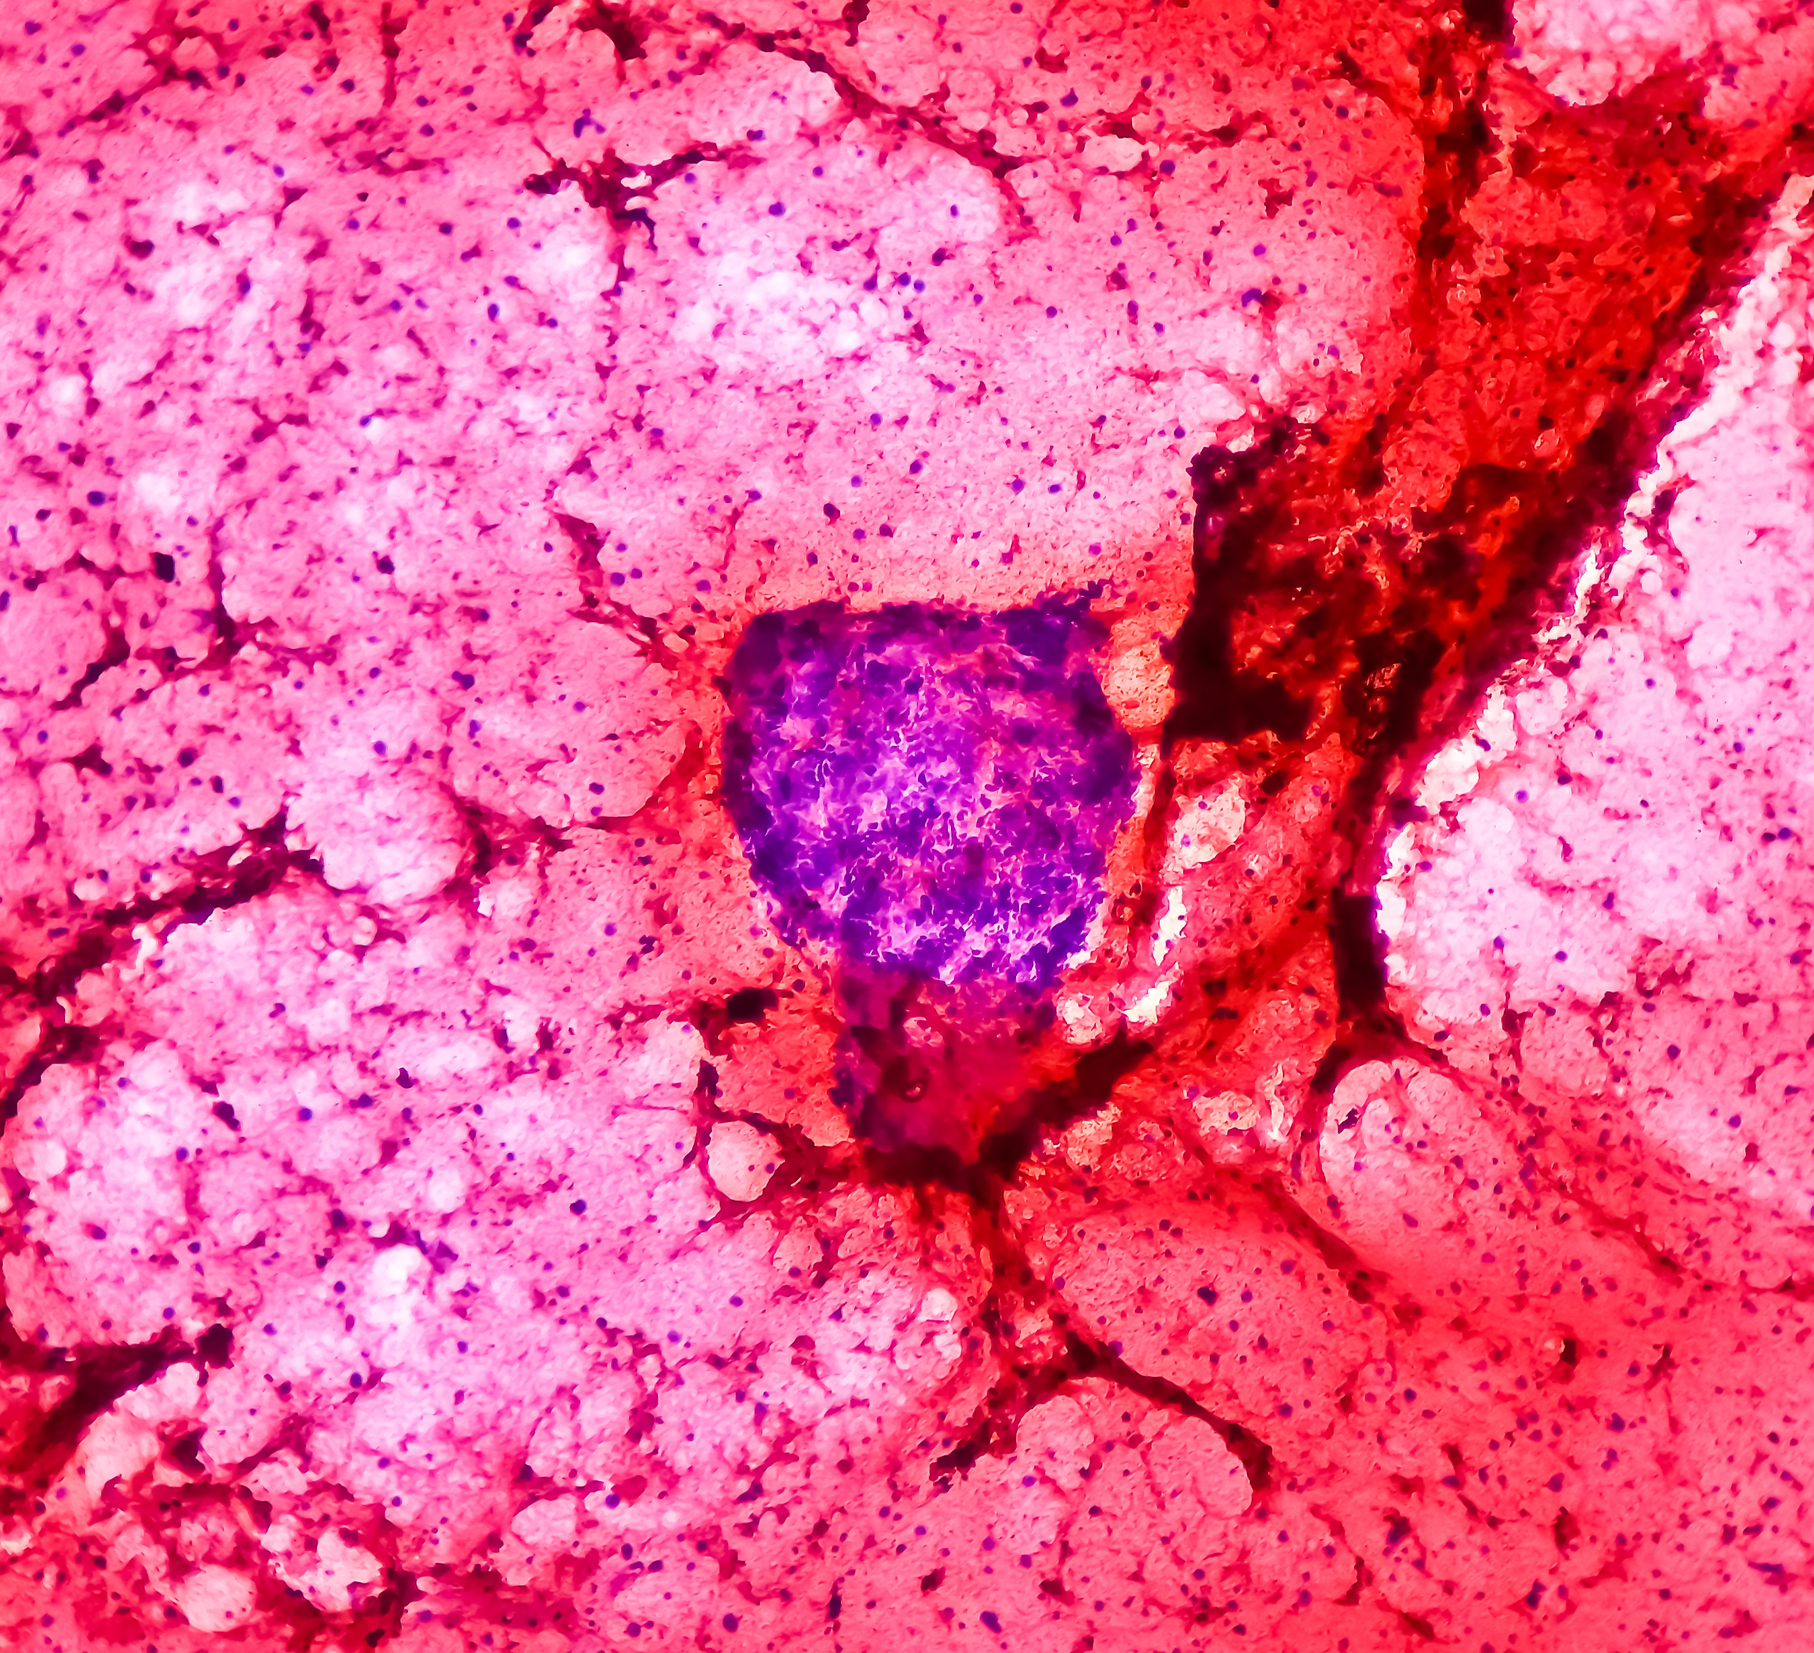

During the biopsy, a pathologist can take a quick look at the sample under a microscope. If it looks like a Ewing tumour, the surgeon can place a small flexible tube into a main blood vessel in the chest during the same operation.